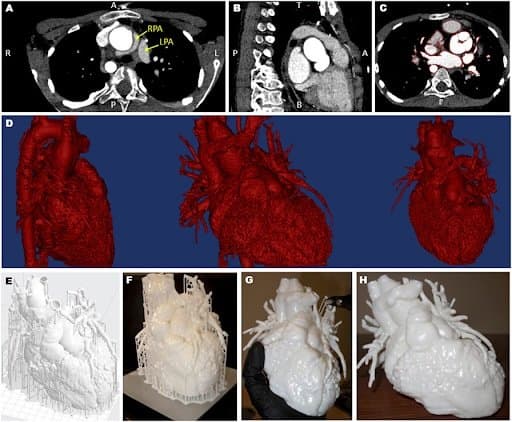

“In order to gather additional insight into the patient’s anatomy prior to the surgery and to facilitate communication with the patient’s parents, a three-dimensional (3D) model of his heart and main vessels was created from computed tomography data. Feedback was collected from different stakeholders.”

“A 3D model was created from computed tomography data… The obtained surface file was further processed using the 3D printer software (PreForm 2.10.3, Formlabs Inc., Somerville, MA, USA), which allowed a scaffold to be automatically created around the model for facilitating the printing process. The model was printed in white resin (Form2, Formlabs Inc.)... The whole process was undertaken at our center, with the 3D printer being available in house.”

Views of the computed tomography imaging dataset (A–C) including highlight of the position of the left and right pulmonary artery (LPA and RPA), showing the RPA wrapping around the aorta (A); the red outline in panel (C) shows the regions included in the three-dimensional (3D) model; the data are then rendered in 3D [(D), showing different views]; a scaffold (E) is built around the model prior to 3D printing (F) and the removed (G), resulting in the final patient-specific model (H).